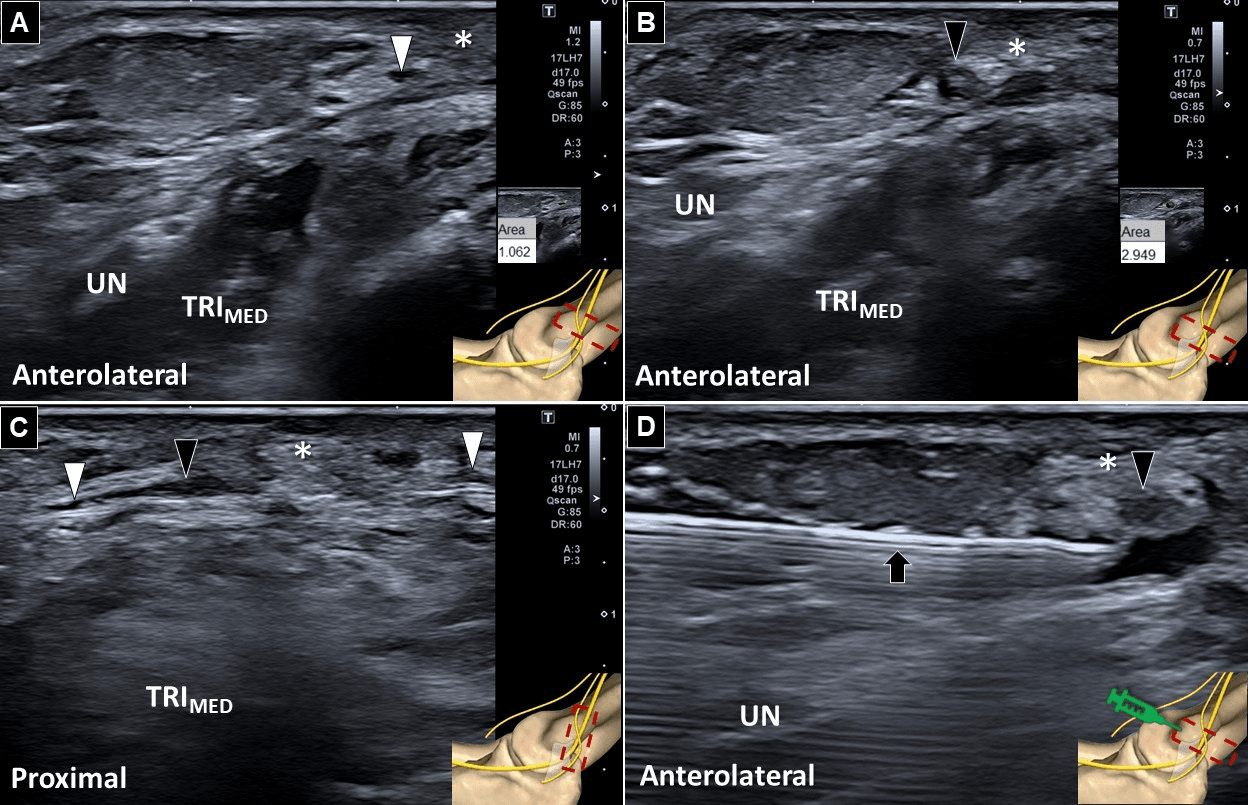

척골신경병증 - 그림 1. 팔에서의 내측 전완피부신경(medial antebrachial cutaneous nerve)의 해부학적 구조 (A)입니다. 단축 초음 Figure 1. 그림 1. 팔에서의 내측 전완피부신경(medial antebrachial cutaneous nerve)의 해부학적 구조 (A)입니다. 단축 초음파-

초음파 검사를 통해 내측 전완피체신경 후분지가 수술 후 흉터 조직 근처에서 국소적으로 비대해진 병리학적 소견을 발견했습니다. 또한 초음파상에서도 양성 티넬 징후가 관찰되어 국소적 신경 자극 진단을 뒷받침했습니다.

척골신경병증 - 그림 2. 초음파검사(ultrasonography)에서 후분지(posterior branch)의 정상 분절을 보여주고 있습니다 Figure 2. 그림 2. 초음파검사(ultrasonography)에서 후분지(posterior branch)의 정상 분절을 보여주고 있습니다

치료는 초음파 유도하에 5% 덱스트로스와 메틸코발라민을 이용한 수압박리술(hydrodissection)을 시행했습니다. 그 결과 시각적 통증 척도(VAS)가 9점에서 2점으로 현저히 감소하는 임상적 호전을 보였습니다.